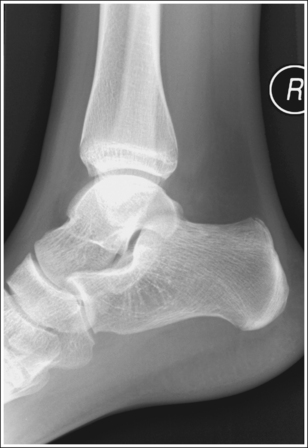

See Figure 6-46 and Box 6-10.

The ankle is demonstrated in an AP projection. The medial mortise (tibiotalar articulation) is open, and the distal tibia and talus are superimposed over the distal fibula by a small amount (0.125 inch [3 mm]), closing the lateral mortise (fibulotalar articulation).

• An AP projection of the ankle is obtained by positioning the patient supine on the image table, with the leg fully extended and the foot dorsiflexed until its long axis is placed in a vertical position (Figure 6-47). In this position, the intermalleolar line (imaginary line drawn between the medial and lateral malleoli) is at a 15- to 20-degree angle with the IR. The medial malleolus is positioned farther from the IR than the lateral malleolus.

• Evaluating the openness of the tibiotalar joint. On an AP ankle projection, determine whether an open joint was obtained and whether the tibia is demonstrated without foreshortening by evaluating the anterior and posterior margins of the distal tibia. On an AP ankle projection with accurate positioning, the anterior margin is demonstrated approximately 0.125 inch (3 mm) proximally to the posterior margin (see Figure 6-48). If the proximal lower leg was elevated or the central ray was centered proximal to the tibiotalar joint, the anterior tibial margin is projected distally, resulting in a narrowed or obscured tibiotalar joint space (see Image 34). If the distal lower leg was elevated or the central ray was centered distal to the tibiotalar joint, the anterior tibial margin is projected more proximally to the posterior margin than on an AP ankle projection, expanding the tibiotalar joint space and demonstrating the tibial articulating surface (see Image 35).

See Figures 6-49, 6-50, and 6-51 and Box 6-11.

Mortise (15 to 20 degrees oblique): The ankle demonstrates 15 to 20 degrees of obliquity. The distal fibula is demonstrated without talar superimposition, demonstrating an open lateral mortise (talofibular joint), and the lateral and medial malleoli are in profile. The fibula demonstrates slight (0.125 inch [33 mm]) tibial superimposition.